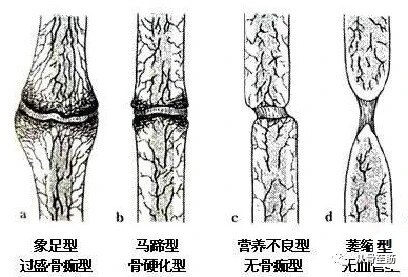

骨折断端局部血液供应情况:骨折部位有充足的血液供应被认为是最重要的因素之一。所以血供较差的部位如:腕舟骨,胫骨中下段,股骨颈等,骨折愈合较慢,很容易形成骨折不愈合。